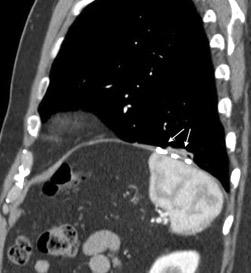

Tromboembolismo pulmonar.

Frecuencia del derrame:

Rx: 32%. TC: 47%

Unilateral. 85%

< 1/3 del hemitórax: 90%

Todos exudados

58% con eritrocitos

21% tabicación lo que causa demora en el diagnóstico

TEP. Empiema pleural. Atelectasia redonda

Porcel JM et al. Analysis of pleural effusions in acute pulmonary embolism: radiological and pleural fluid data from 230 patients. Respirology 2007/ Iguchi T et al. Desquamation of the subpleural lung parenchyma caused by empyema after pulmonary embolism: A case report. Respirol Case Rep. 2022 .

Derrame pleural 43-48% de pacientes con embolismo.

< 1/3 de hemitórax: 90%.(puede haber en lado opuesto).

Siempre exudados.

75% de los pacientes con TEP y derrame pleural tienen dolor pleurítico.